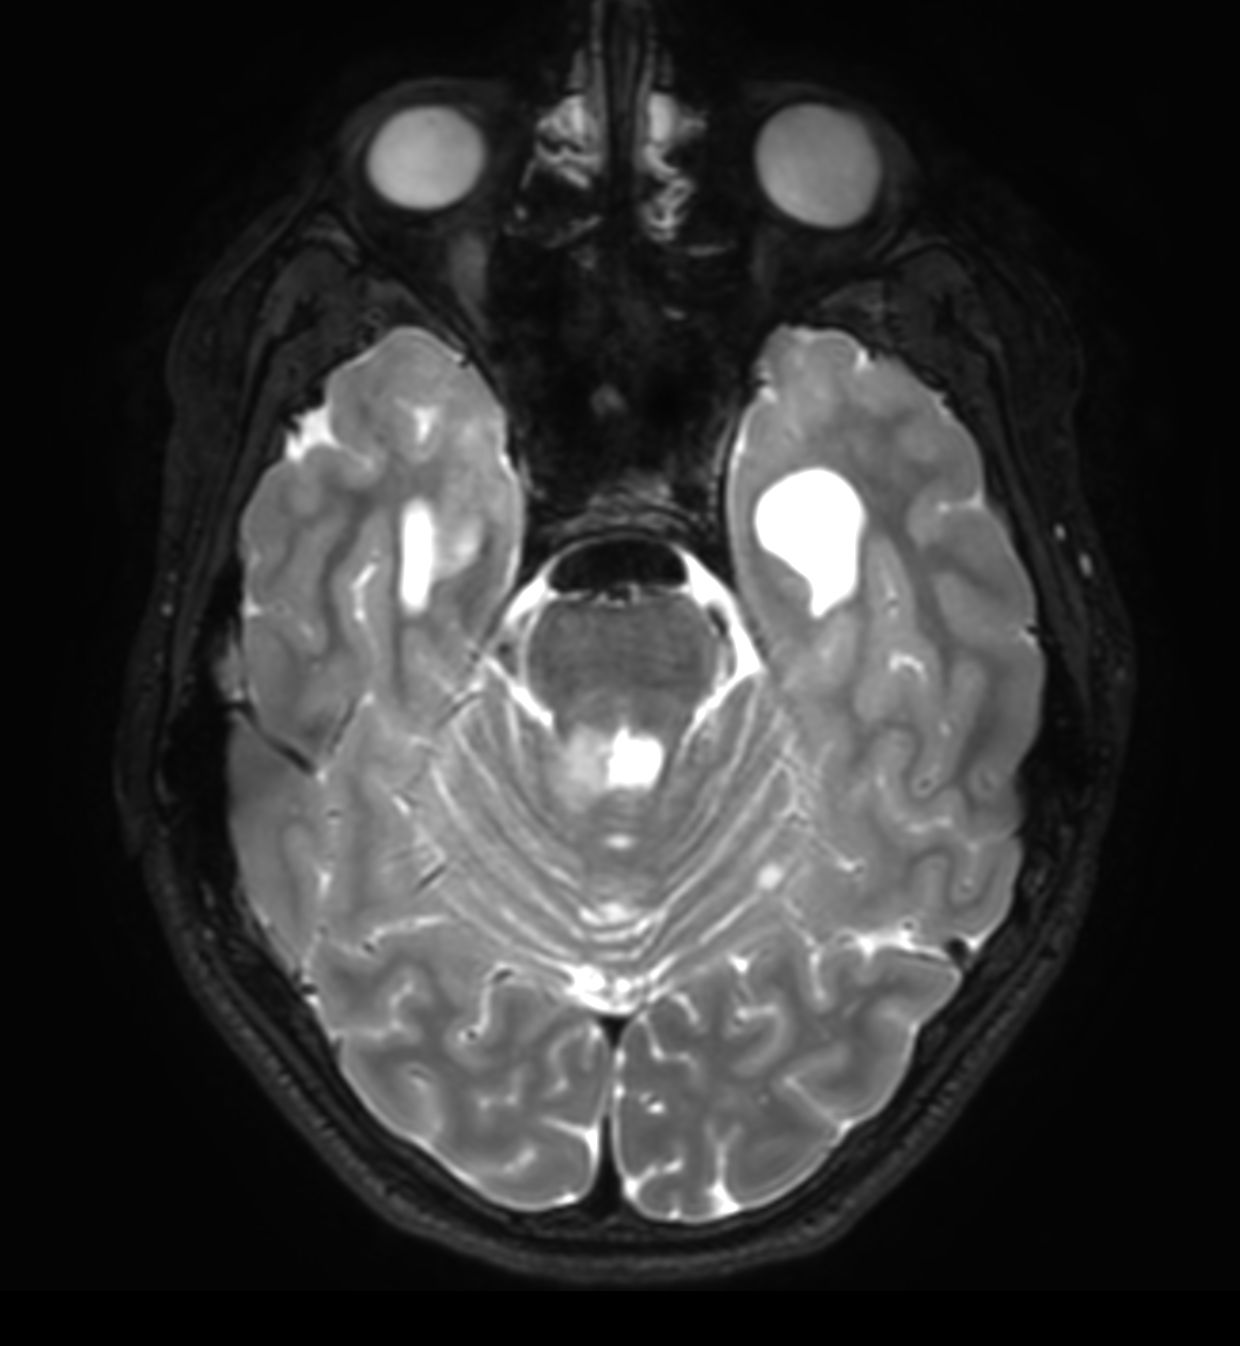

Follow up study of a 12 year old boy with a known low grade glioma.

Axial 3D T2w TSE (reformat)